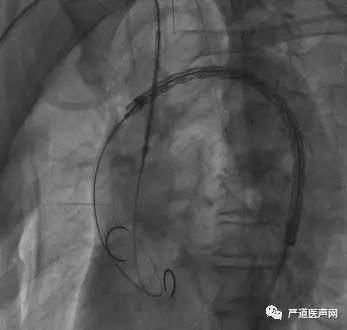

穿刺患者右股动脉,预置2把Proglide缝合器。分段造影证实导丝位于真腔,并沿导管送Lunderquist特硬导丝建立右侧股动脉-升主动脉通道。沿特硬导丝送入1枚戈尔TGU40mm×20cm胸主动脉覆膜支架,并在右侧肱动脉更换为12F动脉鞘,送Lunderquist特硬导丝建立右侧肱动脉-升主动脉通道。

沿肱动脉途径送入一戈尔16mm*14.5mm*7cm髂动脉延伸覆膜支架至头臂干-升主动脉远段,调整胸主动脉覆膜支架近段位置,定位于升主动脉远段-头臂干开口以近处。

TEVAR+ IA chimney—主动脉覆膜支架与头臂干烟囱支架到位

首先释放胸主动脉覆膜支架(如下图),